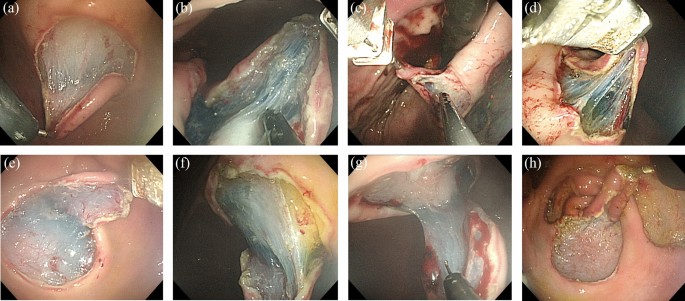

All ESDs were successfully completed in both groups. In the R-ESD group, the robotic arm can be smoothly applied to the workflow of the routine ESD procedure. No critical problem in the coordination between the endoscopist and the assistant was observed during the use of the robot arm. The robot arm worked well without system failures in 16 cases. The robot arm could apply tissue traction in the desired direction and successfully expose the submucosal plane during submucosal dissection in all lesion locations (Fig. 4). No mucosal damage was visible in the pharyngeal or esophageal inlet area after the insertion of the endoscope with the robot arm attached.

Tissue traction and submucosal plane exposure using the robot arm at each lesion location. (a) Upper anterior wall. (b) Upper posterior wall. (c) Upper lesser curvature. (d) Upper greater curvature. (e) Lower anterior wall. (f) Lower posterior wall. (g) Lower lesser curvature; and (h) Lower greater curvature.